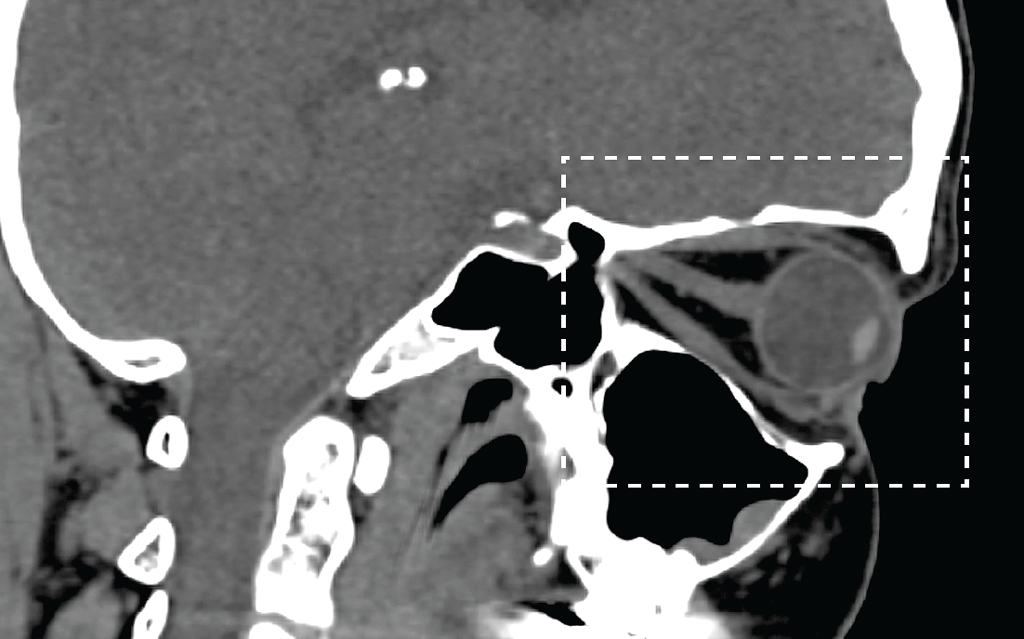

Fig. 21. Eyeball endoprosthetics: a — schematic representation of orbital structures (Э — endoprosthesis, K — nerve stump, Н — external cosmetic prosthesis); b — MSCT of the orbit, sagittal reconstruction, soft tissue window mode, with intravenous contrast, state after endoprosthetics of the left globe. In the anterior part of the left orbit, a centrally located endoprosthesis is visualized (red arrow), round in shape, with homogeneous structure, of 20 mm in diameter, average density of –33 HU, no additional inclusions in the area of the prosthesis were identified, in the anterior part an endoprosthesis capsule with clear, even contours is visualized. An external cosmetic prosthesis (green arrow) is adjacent to the front surface of the endoprosthesis, with the presence of air vacuoles between them

Рис. 21. Эндопротезирование глазного яблока: a — схематическое изображение структур орбиты (Э — эндопротез, К — культя нерва, Н — наружный косметический протез; b — МСКТ орбит, сагиттальный срез, режим мягкотканного окна, с внутривенным контрастированием, состояние после эндопротезирования левого глазного яблока. В переднем отделе левой орбиты визуализируется центрально расположенный эндопротез (красная стрелка), округлой формы, однородной структуры, диаметром 20 мм, средней плотностью –33 HU, дополнительных включений в области протеза не выявлено, в передней части визуализируется капсула эндопротеза с чёткими ровными контурами. К передней поверхности эндопротеза (к опорной культе) прилежит наружный косметический протез (зелёная стрелка), с наличием вакуолей воздуха между ними